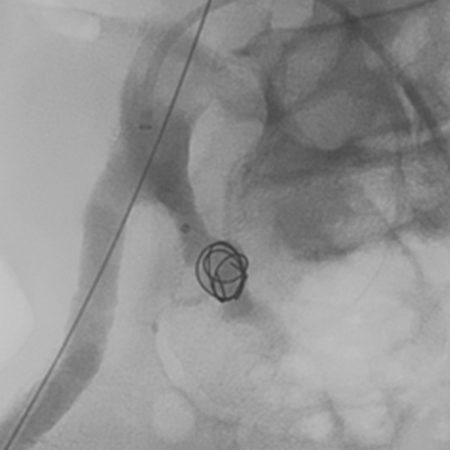

Peripheral embolization

Radiolucent, Minimal Artifact

Facilitates visibility during and after the procedure